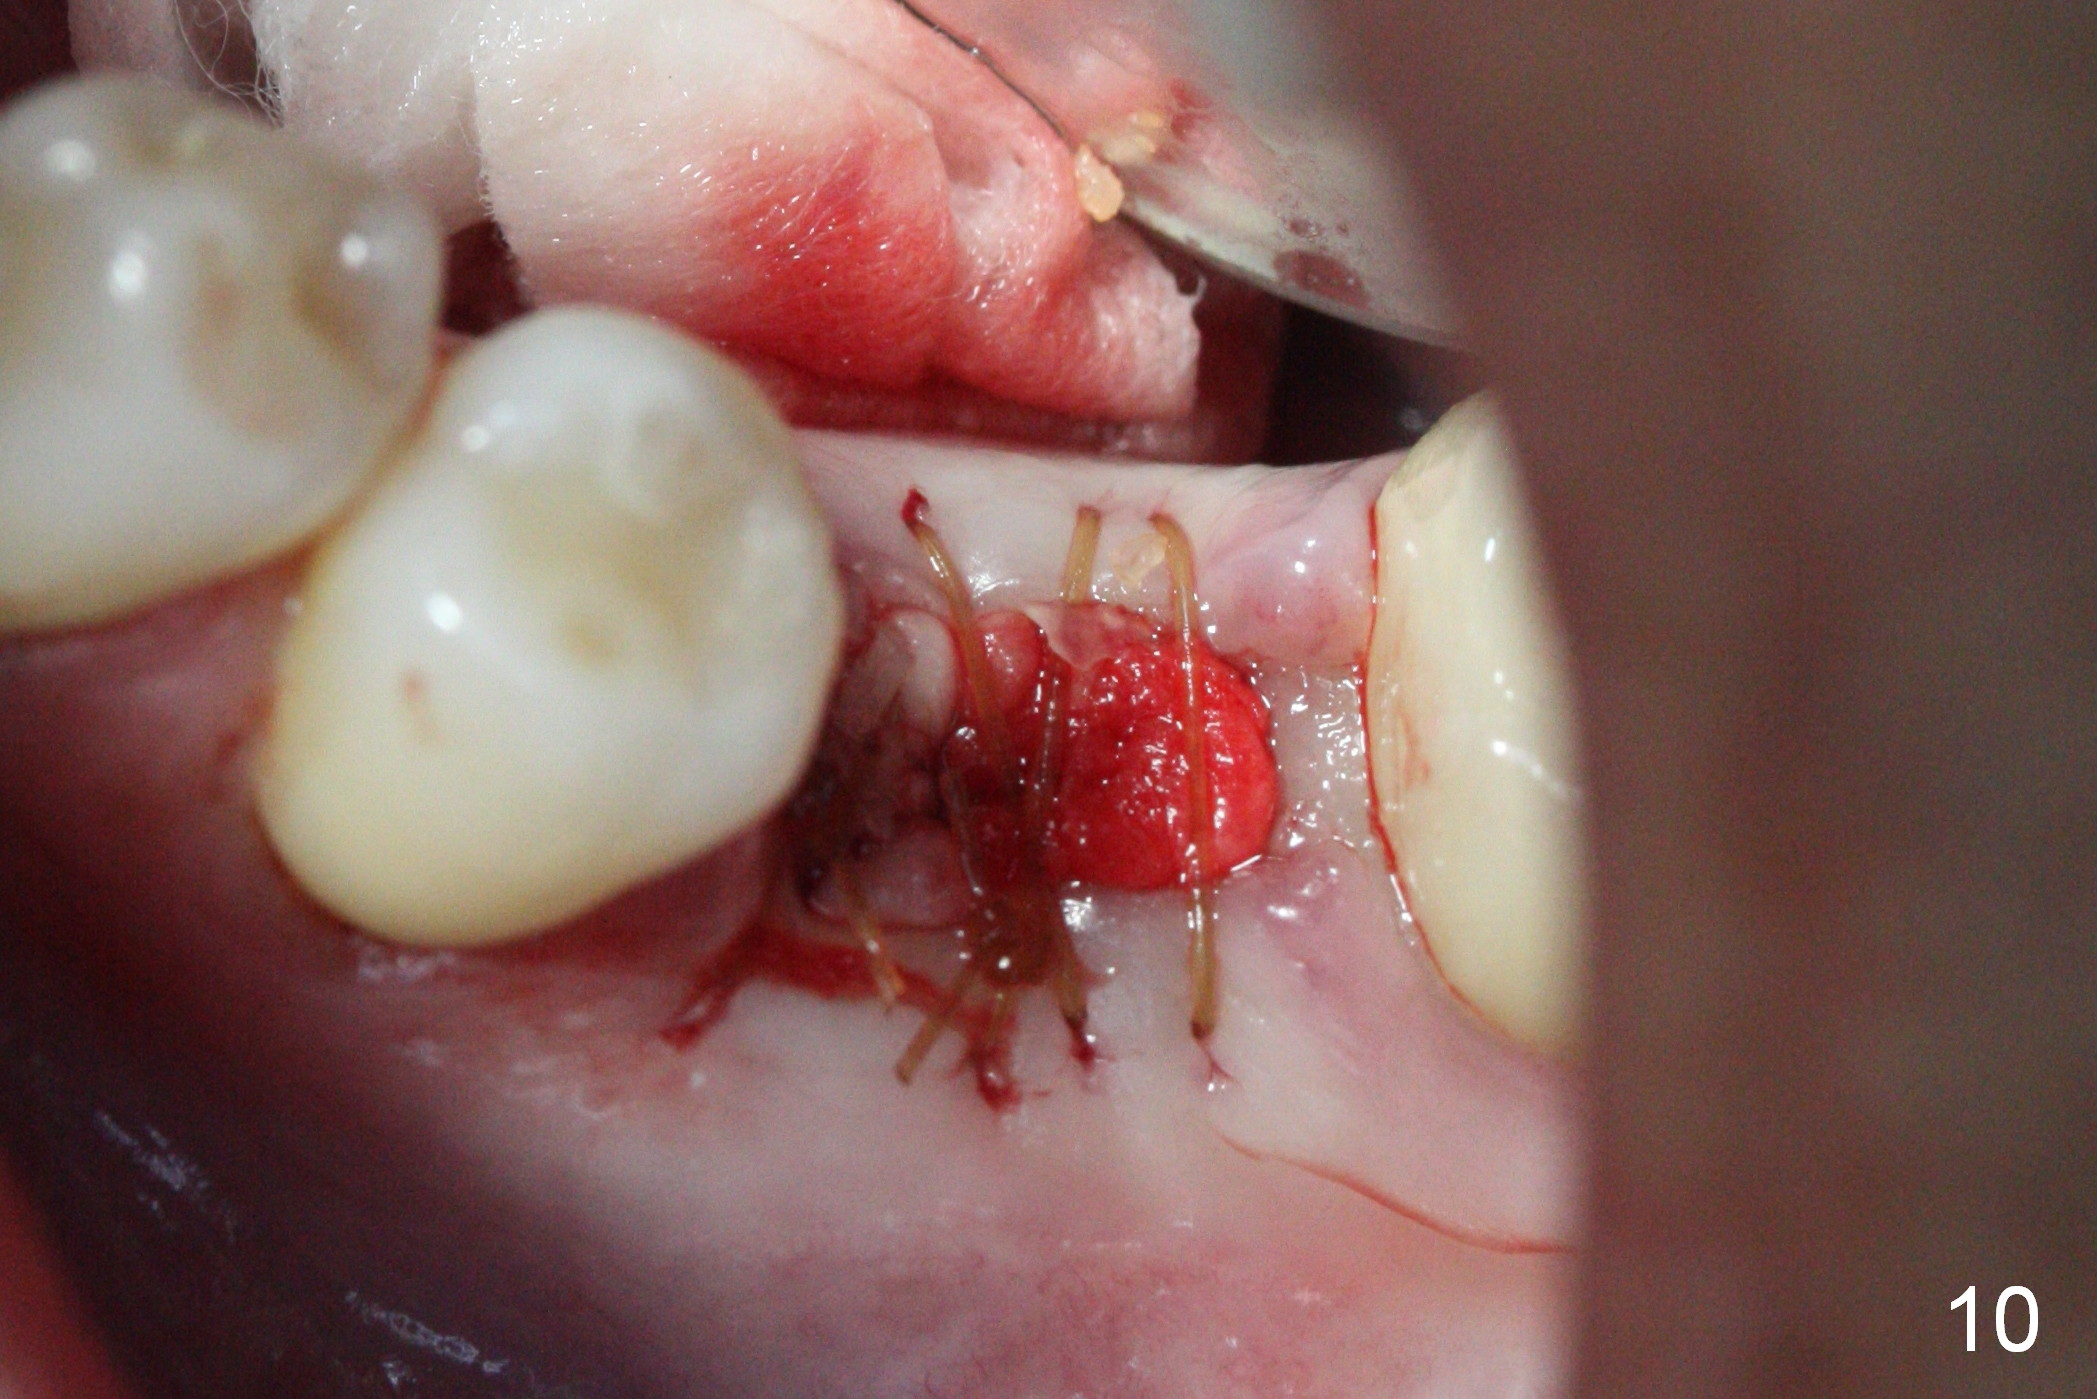

The tooth #19 is easy to get loose, but it cannot be luxated.  After sectioning and extraction (Clindamycin), the septum is found to be thin (Fig.4).  A surgical fissure bur is used to initiate osteotomy, followed by 1.6 mm pilot drill.  It is difficult to use Marking bur (wobbling over the basically pointed septum).  It is impossible to use 4.3 mm Magic Drill (MD, one drill system), since it jumps.  The smallest MD has to be used (2.8 mm).  When the next drill (3.3 mm) is being used for 13 mm with stopper (Fig.5), the patient experiences transient pain.  The depth is suggested from the design in Fig.2.  The thin septum appears not to be a reliable landmark.  When block anesthesia is administered, the initial depth should be shortened.  The drill appears to be close to the Inferior Alveolar Canal (Fig.5).  Then the depth changes to 11 mm with the following drills (3.8 and 4.3).  The mesial and distal walls of the septum are gradually perforated.  A 5x9 mm dummy implant is placed only after using 4.8 mm drill (Fig.6).  The implant appears to be short.  When a longer implant is placed (5x11 mm), it does not easily enter the osteotomy, either sliding into the mesial or distal socket with the implant separating from the implant driver.  It appears that a premount implant is appropriate in this situation.  When the 5x11 mm implant is finally seated with stability, it is 6 mm apical to the gingival margin.  The longest cuff of IBS abutment is 4 mm.  A longer implant is needed (Fig.7, 5x13 mm).  Placement is not easy as mentioned above.  Insertion torque is <20 Ncm when the patient experience a little discomfort.  A 6.5x4(4) mm pair abutment is placed (A), apparently proper for restoration.  Allograft is placed (Fig.8 *) prior to immediate provisional.  The patient complains of bad smell from the site 24 days postop.  When the provisional is removed, the abutment is found to be mobile.  When the latter is removed with local anesthesia, bone graft granules are attached to the socket above the lightly mobile implant (Fig.9).  In fact the latter appears to be stable after a few turns by finger.  A healing screw is placed; the socket is closed with collagen plug and 4-0 Chromic gut sutures (Fig.10).  It appears that a larger implant should have been used to achieve higher torque.  Two months later (3 months postop), the coronal end of the implant is partially exposed.  A 5x4 mm healing abutment is placed.  It appears that the implant is stable.  The implant appears to have osteointegrated 4 months postop (Fig.11).  Impression is taken.